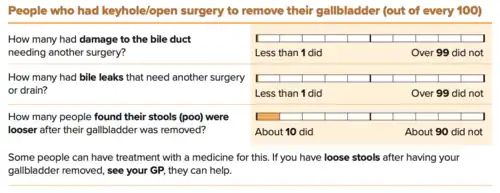

Surgical

Cholecystectomy (gallbladder removal) has a 99% chance of eliminating the recurrence of cholelithiasis. The lack of a gallbladder has no negative consequences in most people, however 10 to 15% of people develop postcholecystectomy syndrome,[48] which may cause nausea, indigestion, diarrhea, and episodes of abdominal pain.[49]

There are two surgical options for cholecystectomy:

- Open cholecystectomy is performed via an abdominal incision (laparotomy) below the lower right ribs. Recovery typically requires 3–5 days of hospitalization, with a return to normal diet a week after release and to normal activity several weeks after release.[54]

- Laparoscopic cholecystectomy, introduced in the 1980s, is performed via three to four small puncture holes for a camera and instruments. Post-operative care typically includes a same-day release or a one-night hospital stay, followed by a few days of home rest and pain medication.[54] Perforation of the gall bladder is not uncommon—it has been reported in the range of 10% to 40%. Unretrieved gallstone spillage has been reported as 6% to 30%, but gallstones that are not retrieved rarely cause complications (0.08%–0.3%).[55]